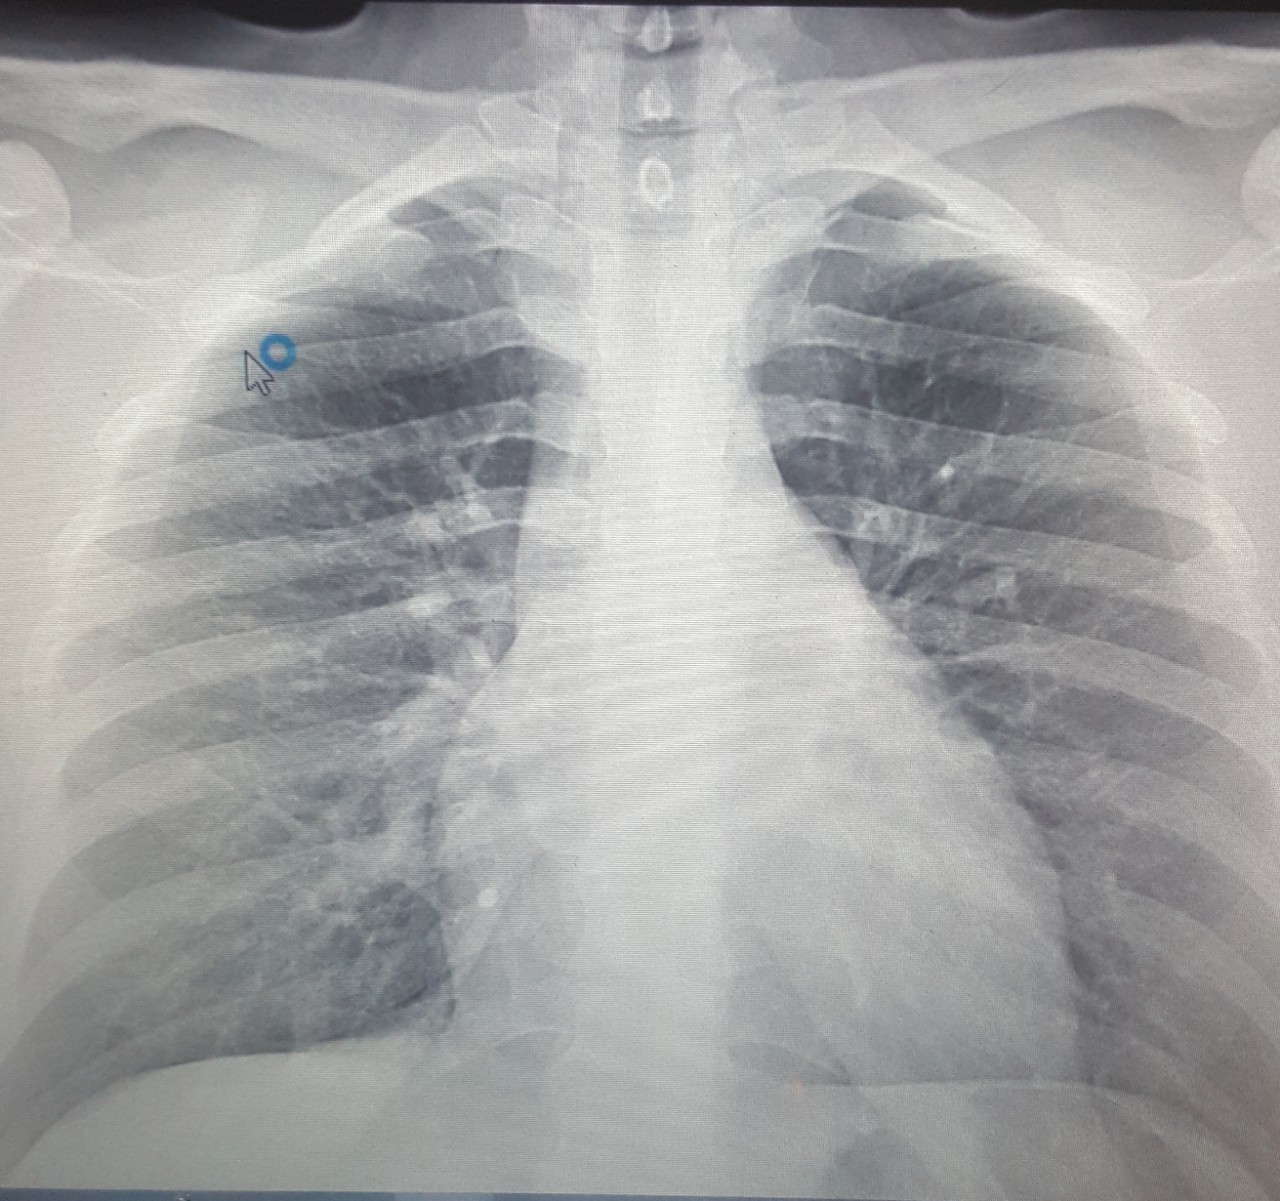

Нормальная рентгенограмма легких: что нужно знать

Раздел: Мудрость в объективе